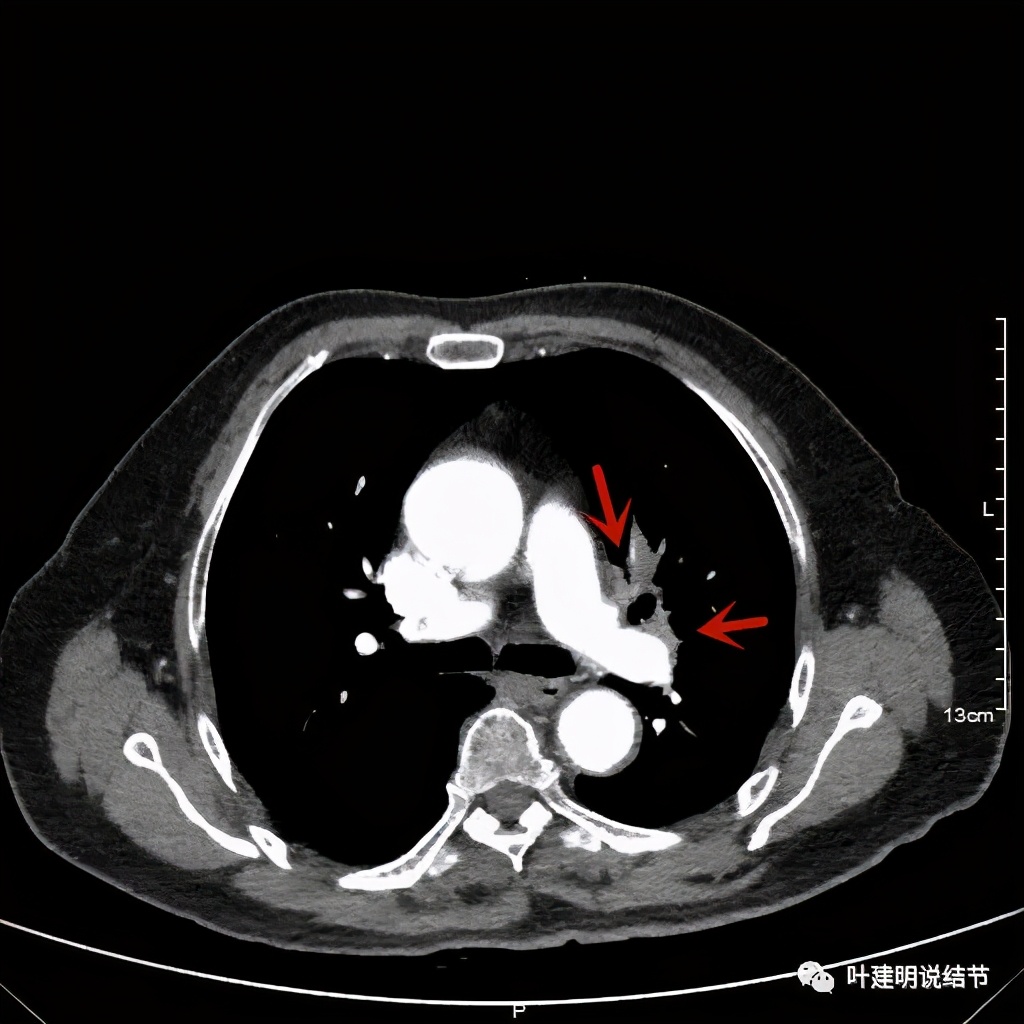

上图示肿瘤部位仍与肺动脉关系密切,似乎未能脱开,红色示肿瘤处